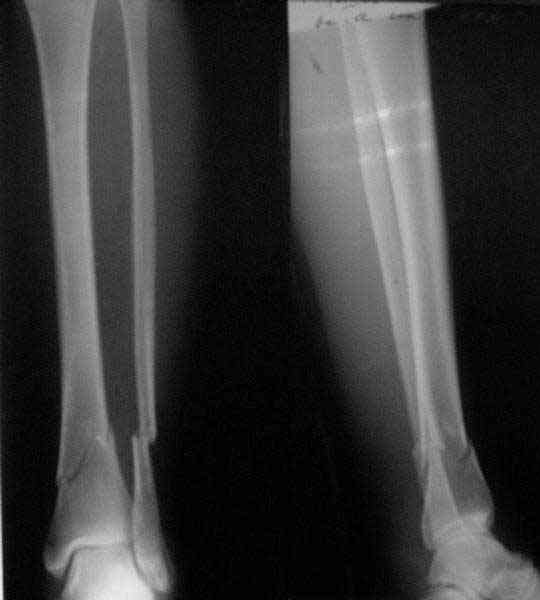

In delayed cases acute length restoration performed only in the tibia may leave the fibula shortened thus change the mortise. So it is reasonable to restore length of both bones simultaneously by distractor and fix the fibula not with open reduction and plating but just by a single perQ screw. Example attached.